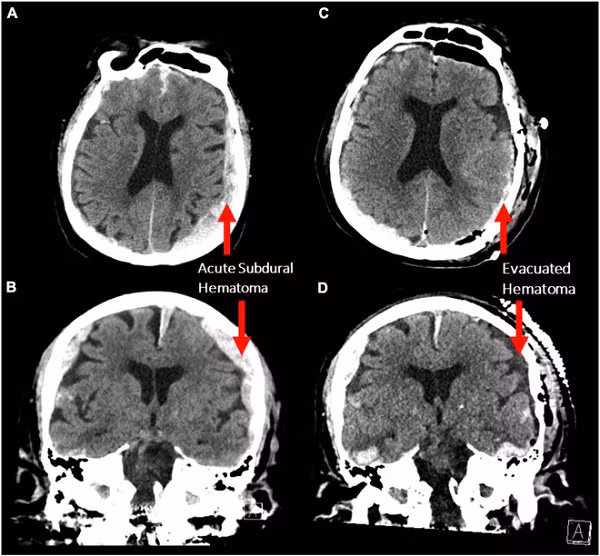

Theo đài Sputnik (Nga), nghiên cứu trên được thực hiện một cách tình cờ ở một người đàn ông 87 tuổi mắc chứng động kinh. Trong quá trình phẫu thuật, bệnh nhân lên cơn đau tim và qua đời nhưng chiếc máy vẫn tiếp tục hoạt động, ghi lại hoạt động não.

Cụ thể, trong 900 giây sóng não được ghi lại, các nhà khoa học nhận thấy ngay trước và sau khi tim ngừng đập, hoạt động của não tăng lên tương tự như những gì xảy ra khi chúng ta tập trung, mơ, nhớ lại ký ức và thiền định.

Thêm vào đó, loại sóng não cụ thể được ghi lại trong bộ não sắp chết - được gọi là dao động thần kinh - cho thấy người đó đang nhìn thấy cuộc sống của họ lóe lên trước mắt thông qua cơ chế "truy xuất bộ nhớ".

“Bộ não của con người có thể vẫn hoạt động và liên kết với nhau thậm chí sau khi cơ thể chuyển sang trạng thái tim ngừng đập. Thậm chí, trong khoảnh khắc đó, bộ não còn có thể được lập trình để sắp xếp lại toàn bộ ký ức” - các nhà nghiên cứu cho hay.

Ông Ajmal Zemmar – nhà giải phẫu thần kinh tại Đại học Louisville, người đứng đầu nghiên cứu cho biết, phát hiện này đặt ra câu hỏi liệu sự sống có được “thắp lên” trong những phút cận tử. Nó cũng đồng nghĩa với việc, trong giờ phút cận tử, bộ não con người có thể đang nhớ lại một số khoảnh khắc đẹp nhất từng trải qua.

Tuy nhiên, nhiều ý kiến cũng cho rằng cần có thêm những đối tượng nghiên cứu mới. Bởi đây mới là kết quả trên một người đàn ông mắc chứng động kinh. Não của bệnh nhân này đã bị tổn thương do co giật và phù nề, điều này làm phức tạp thêm việc giải thích dữ liệu. Chúng ta vẫn cần chờ đời nhiều hơn trong tương lai.